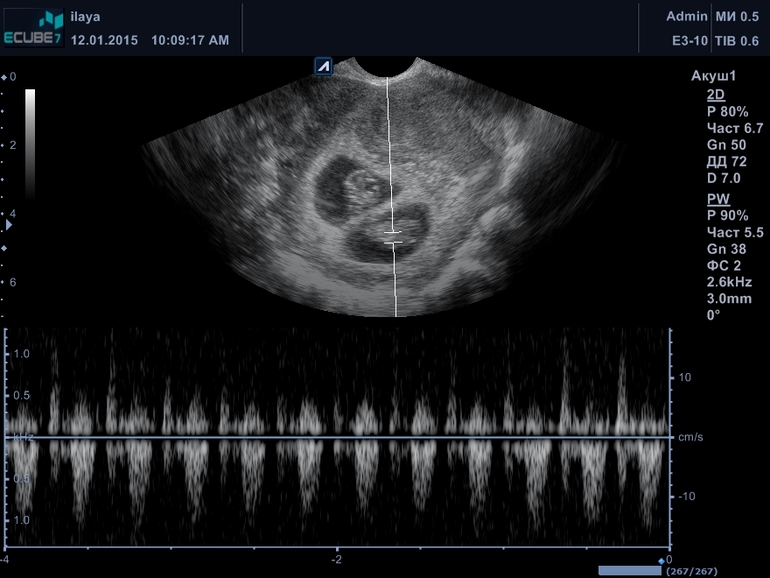

Моя ЭКО-история (от начала пути до родов)Около 30 лет назад... когда мне было всего 5 лет... вырезали мне аппендицит.. был перетонит. 2 переливания крови и 2 операции.. короче жизнь спасли, но спаечный процесс остался. В 2010 году удаление кистомы с правого яичника, правда яичник почти целым оставили. Потом 2 года мытарств по докторам с дисбиозом и безрезультатно 3 степень чистоты мазка и хоть ты тресни.. В 2012 году свадьба и попытки забеременнеть в течении года. Поиск репродуктолога.. сначала медгородок г. Киева на пр-те Комарова .. там доктор Довгалева Анна Николаевна ( хороший доктор тел 050 510-12-74).у которой я наблюдалась 2 года... сдали гормоны, спермограмму... вердикт- и гормоны и спермограмма отличные.. проблема-спаечный процесс из детства после аппендицита, трубы непроходимы, требует ЭКО. При выборе клиники ЭКО долго перебирали в интернете отзывы и никак не могли определиться. Наконец знакомая посоветовала клинику "Мать и дитя" доктора Ковалевскую Ларису Станиславовну. Сходили на прием. У них требование... чтобы спермограмму у них в клинике сдавали. Короче пришли... Лариса Станиславовона говорит мне.. что у меня гормоны не в норме. Я говорю в норме, вот ананализы, она а тут еще вот нескольких гормонов нет, а я точно уверена что они не в норме. Спермограмма показала что у мужа бесплодие.. на мой вопрос, а что могла случиться за 6 месяцев с мужем если он ничем не болел, в зоне радиации не был, с химией дел не имел, не перегревался чтобы со 100% осталось живых меньше 40%. Она не смогла ответить, зато мне сказала ложиться на узи.. посмотрела на узи и говорит.. у вас жидкость в брюшной полости.. я говорю как это? она показывает.. ну говорю что делать, а она мне свечи поставте.. (жидкость в брюшной полости требует экстренной операции-это перитонит)...Вообщем предложила она нам ЭКО+ИКСИ.. Мы сказали что подумаем... Вышли и оба как-то очень засомневались в поставленных диагнозах. Уж очень смахивает на развод, при чем не очень грамотный.. Но на всякий случай съездили в областную на Боггоутовскую к узисту Бокучаве Руслану Александровичу ( ему доверяют хирурги, а это многое значит) тел. 097-404-29-35, приезжаю говорю жидкость у меня там.. он долго смотрел.. кряхтел и спрашивает, а кто сказал я говорю такая-то .. он -ясно.. поворачивает монитор и показывает .. на темное пятно.. спрашивает.. вот эту жидкость показали.. я ему -ага. а он отвечает... запомни это твой мочевой пузырь. Мы с мужем посмеялись, погоревали.. как искать кому доверять и решили в отпуск съездить . Незадолго до отпуска я решила сходить в клинику ЭКО возле дома. Пошли в клинику "Илая" к первому попашемуся доктору ( прием первый бесплатный) Бабенко Ирине Владимировне , г. Киев, тел. 097 729-29-27. Она послушала нас, посмотрела спермограммы и говорит.. спермограмму пересдать. У тебя все ок, только спайками затянуто и бесперспективно их разъединять поскольку перитонит был давно.. трубы развивались в спайках, они крученные перекрученные скорее всего, а значит даже если распутать то ворсинки которые передвигают яйцеклетку поврежденны и риск внематочной велик. Но если хочешь сделай лапару по рассоединению и пробуй. Но мой совет -ЭКО поскольку тебе за 30 и резерв яйцеклеток уменьшается и шансы даже на ЭКО уменьшаются. Вот только надо удалить полип в матке... Вообщем съездили в отпуск, сдали спермограмму- все ок! сделали мне гистероскопию-удалили полип и в феврале 2014 пошли в протокол... взяли 8 яйцеклеток получилось 5 эмбрионов, 2 подсадили на 3 день-пролет. В апреле 2014 пошли в криопротокол- 3 пятидневки подсадили и...пролет. Муж решил разводиться со мной, у меня от гормонов начался зуд на коже , дерматит и демодекоз, нервы сдали, ну думаю все капец. Надо думать об усыновлении. Вот думаю поеду в отпуск-полечу грязями кожу, приеду разведусь и пойду по детдомам, по службам специальным буду усыновлять... Ирина Владимировна как узнала что муж меня бросает, распереживалась...поддерживала меня морально очень. Но у мужа оказалась истерика.. Видимо мужчины тяжелее переносят стресс или я просто сильная))) Вообщем желание развестись было недолгим-около 2 недель. Потом извинения, мольбы и прочее.. Короче простила я его и осенью решили снова пробовать. Съездили в отпуск. В отпуске были с моей подругой которая подала на развод и по приезду из отпуска получила развод. И так мне ее было искренне жаль что от всего сердца попросила я у Боженьки ей если не мужа то хотя бы мужика хорошего в отпуске и ребеночка славного от него. И Боженька услышал... был у подруги и мужчина и малыш сейчас подрастает уже 4 месяца как))) Вообщем по приезду из отпуска чуток еще поработали, денег поднапряглись поднасобирали и в ноябре 2015 в протокол второй пошли.... 28 ноября пункция 7 яйцеклеток, 6 эмбрионов, 2 декбря перенос 3 пятидневочек на 7 день после переноса еле заметная полоска на тесте, 17 декабря 2014 ХГЧ 1995, а 29 декабря 2014 года подарок к Новому году... две козявочки на экране монитора УЗИ, 31 июля 2015 года родились дочь Ольга и сын Илья.